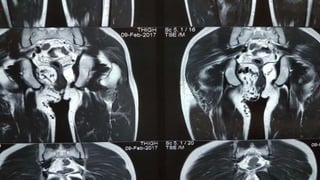

MRI

A LARGE 11.7x10.8x5.9cm AVM

IN RIGHT GLUTEAL REGION

THE LESION IS EXTENDING TO

THE ISCHIORECTAL AND

PERIANAL SPACE WITHOUT ANY

EXTENSION TO THE

INTERSPHINCTERIC REGION

FEEDING FROM BRANCHES OF

RIGHT INTERNAL ILIAC ARTERY

AND DRAINING INTO INTERNAL

ILIAC VEIN

RADIOLOGICAL INVESTIGATIONS USG ARTERIOVENOUS MALFORMATION INTHE RIGHT GLUTEAL MUSCLES MRI A LARGE 11.7x10.8x5.9cm AVM IN RIGHT GLUTEAL REGION THE LESION IS EXTENDING TO THE ISCHIORECTAL AND PERIANAL SPACE WITHOUT ANY EXTENSION TO THE INTERSPHINCTERIC REGION FEEDING FROM BRANCHES OF RIGHT INTERNAL ILIAC ARTERY AND DRAINING INTO INTERNAL ILIAC VEIN